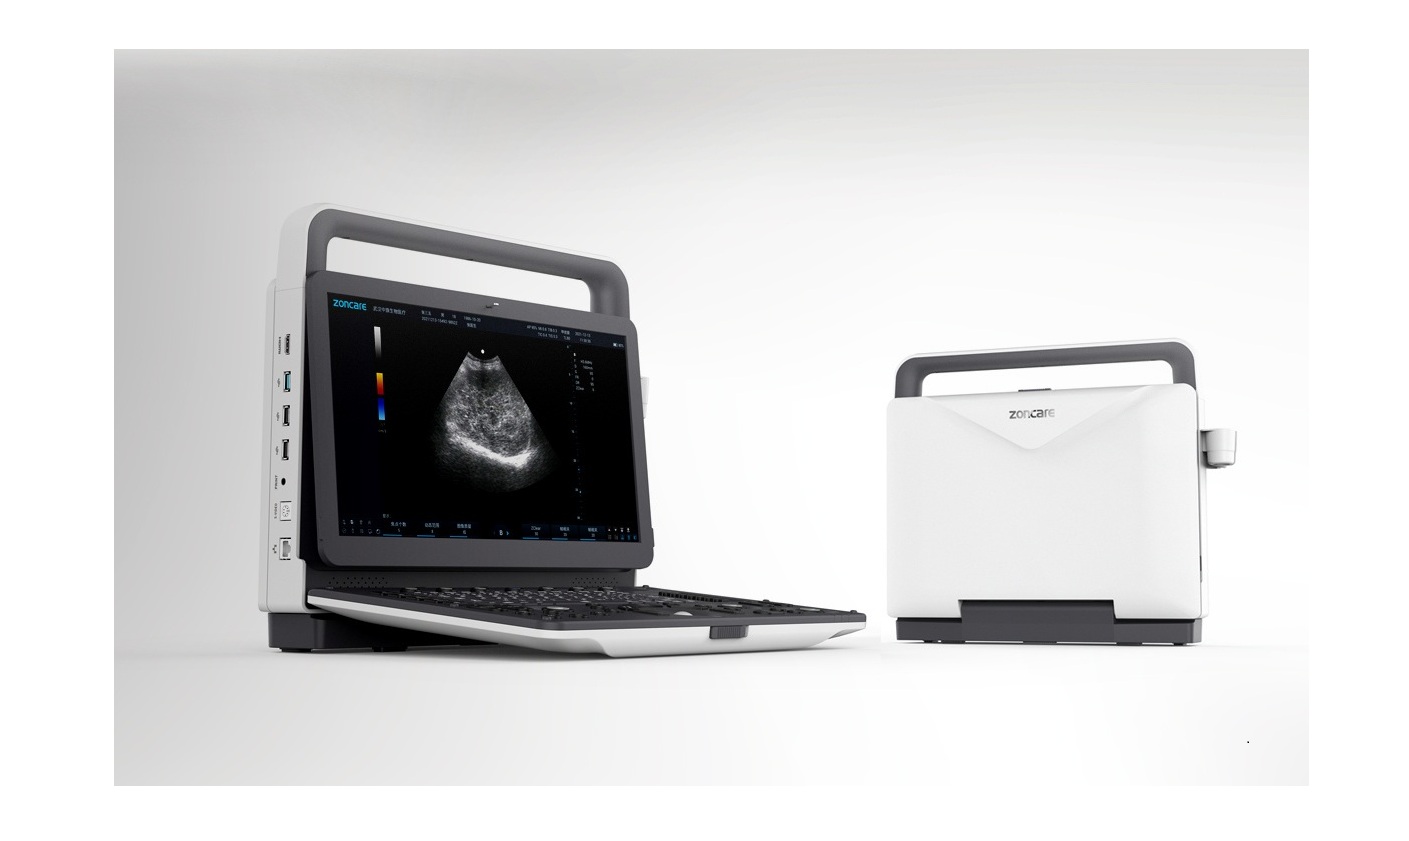

B.S.D. M70 – 3D-4D Ultrasonido Doppler Color Portátil

El ecógrafo portátil B.S.D.M70 combina tecnología de imagen avanzada con el algoritmo inteligente uSeed, ofreciendo una calidad de imagen superior para diagnósticos confiables en una amplia variedad de aplicaciones clínicas. Su diseño híbrido —capaz de funcionar tanto como sistema de escritorio como equipo portátil— lo convierte en una solución versátil para hospitales, clínicas y unidades móviles de atención.

La movilidad mejorada del BSD. M70 facilita su desplazamiento entre áreas clínicas o consultas externas, sin sacrificar rendimiento. Con funciones completas de medición, modos avanzados de imagen y compatibilidad con múltiples sondas, el BSD. M70 es una herramienta de diagnóstico integral diseñada para profesionales que requieren portabilidad, precisión y eficiencia en un solo dispositivo.

Especificaciones Físicas

-

Dimensiones: 380 × 361,5 × 157,2 mm

-

Peso: aprox. 6,45 kg (sin batería)

-

Puertos de sonda: 3 (activados)

-

Alimentación: 100–240 V / 50–60 Hz / 150 VA

-

Batería: 14,4 V / 6500 mAh

-

Sistema operativo: Linux